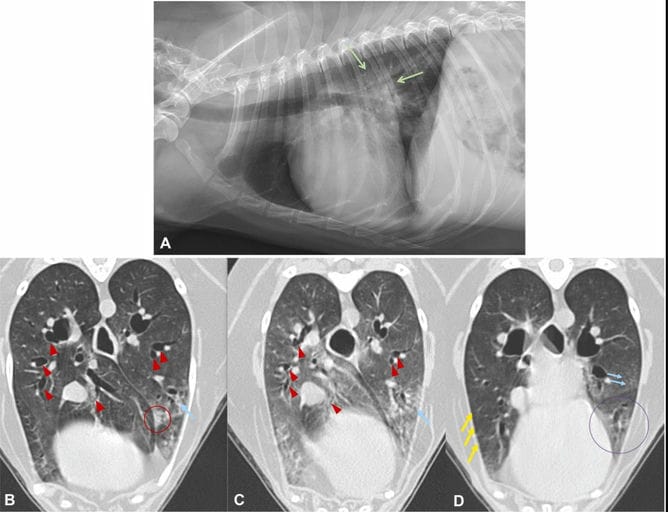

A-D. An example of multiple CT patterns and subpatterns identified in a 14-year-old female mixed breed dog, presenting for increased respiratory rate. The patient had been previously diagnosed with mitral and tricuspid valvular degeneration and was taking twice daily furosemide; an echocardiogram performed the same day as these images showed stable ACVIM Stage B2 degenerative valve disease. A) Right lateral thoracic radiograph depicting mild, caudally distributed unstructured interstitial pattern (arrows). Images B) and C) represent transverse inspiratory and expiratory images, respectively, at the level of the cardiac apex. There is moderate-marked collapse of the segmental and subsegmental airways diagnostic for bronchomalacia (red arrowheads, C), a region of consolidation within the left caudal lung lobe (red circle, image B), and peribronchovascular thickening (blue arrows, B, C, and D). D) A transverse inspiratory image slightly cranial to (B) and (C) illustrates a region of ground-glass opacity within the cranial subsegment of left cranial lung lobe (purple circle) and peribronchovascular thickening in the left caudal lung lobe (blue arrows). Subpleural interstitial thickening is present in the right middle lung lobe (yellow arrows).